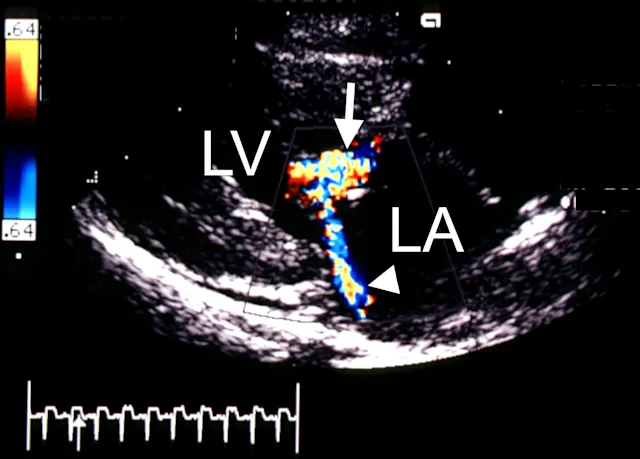

Once the patient is stabilized (often after 12 to 24 H), obtain radiographs (Figure 3) and echocardiography to confirm the diagnosis of CHF and to identify the nature and severity of the cardiac disease. The most common cause of CHF in cats is HCM; less common are dilated, restrictive, and unclassified cardiomyopathy. Murmurs associated with HCM are usually created by mitral regurgitation, abnormal displacement of the mitral valve during systole (systolic anterior motion or SAM), causing left ventricular outflow tract obstruction, or dynamic right ventricular obstruction either in combination (e.g., mitral regurgitation is always present with SAM) or alone (mitral regurgitation can also occur without SAM) (Figure 4).

FIGURE 4A Two-dimensional, right parasternal, long-axis view of the heart in a cat with HCM and pleural effusion. Note the large thrombus in the left atrium